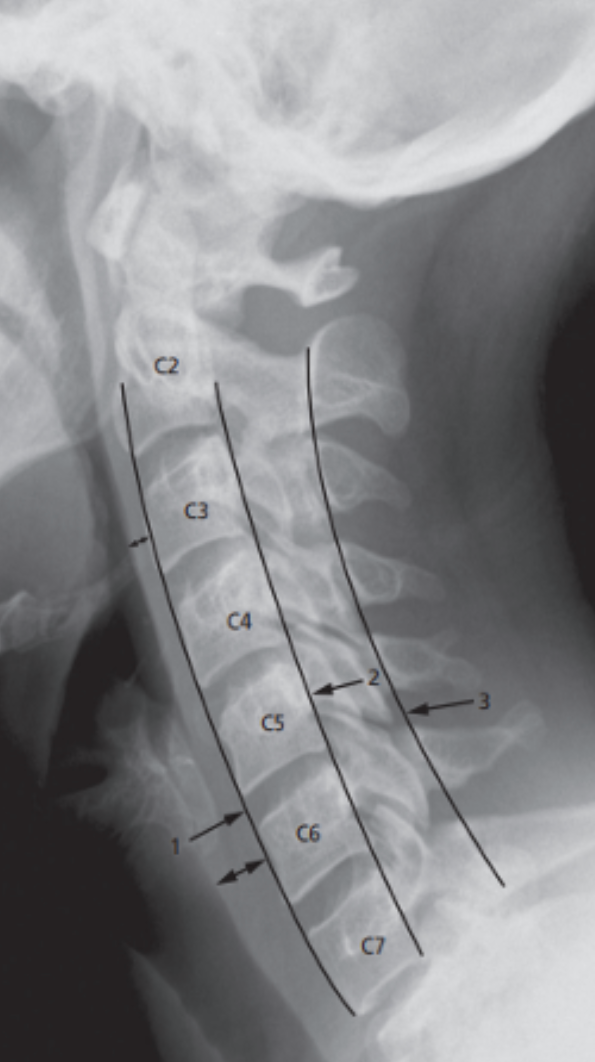

Normal cervical spine (CC TB)

showing lines to check alignment.

Line 1: runs along the anterior border of the vertebral bodies and corresponds to the anterior longitudinal ligament.

Line 2: runs along the posterior border of the vertebral bodies (posterior longitudinal ligament).

Line 3: runs along the junction of the laminae and spinous processes. (Spinolaminar line)

Line 2 & 3: Line 2 indicates the anterior extent and line 3 the posterior extent of the spinal canal.

There is a normal soft tissue distance between the anterior border of the spine and the posterior border of the airway (double-headed arrows)